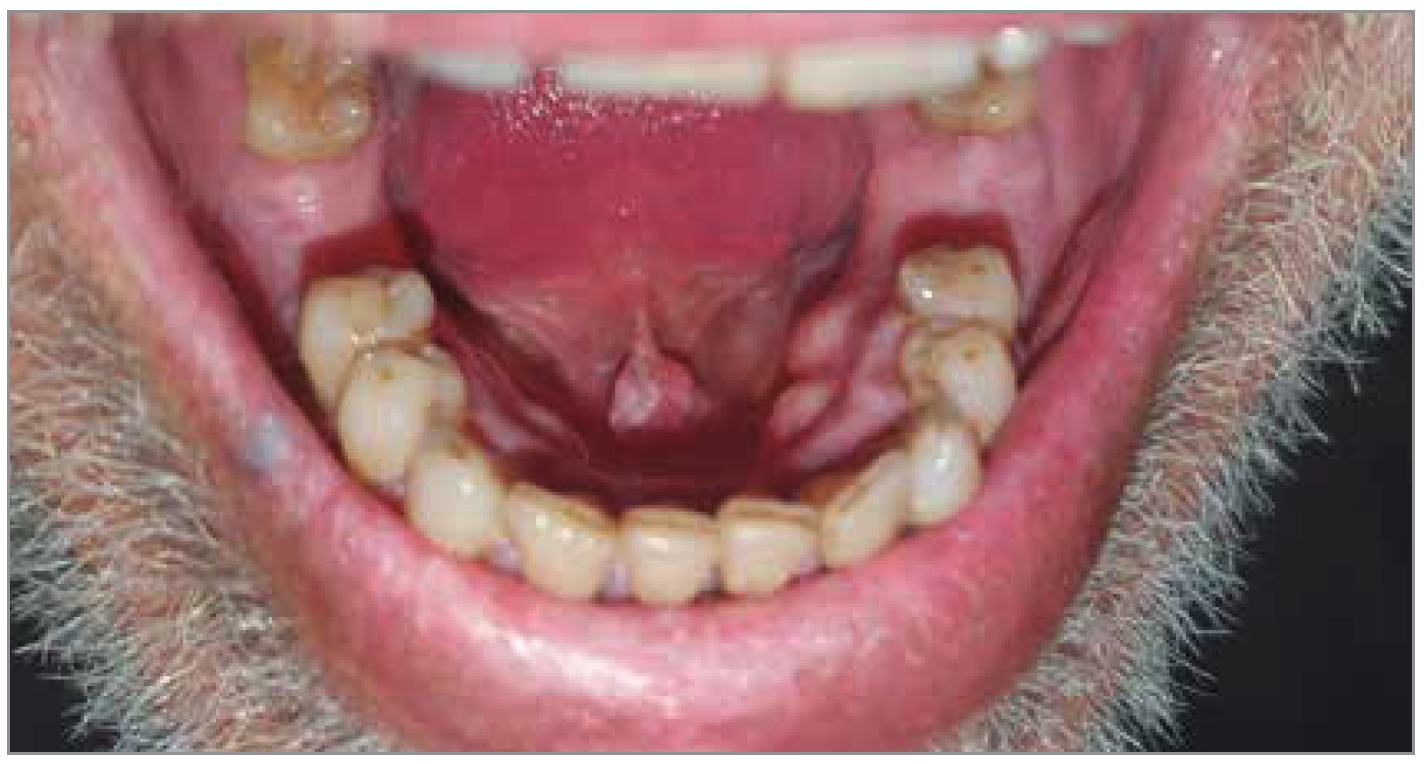

À l’examen de la cavité buccale, nous avons pu constater la présence d’une formation tumorale de couleur blanche, et bourgeonnante (Fig. 1). Le reste de l’examen s’est révélé tout à fait normal. Par ailleurs, nous avons palpé une adénopathie de plus de 2 cm au niveau de la région cervicale.

Figure 1 – Leucoplasie verruqueuse du frein de la langue (flèche rouge).

La lésion du frein de la langue correspondait quant à elle à une leucoplasie verruqueuse. Cette dermatose doit nous inciter à rechercher une lésion maligne sous-jacente de type carcinome épidermoïde (comme cela a été le cas pour notre patient).